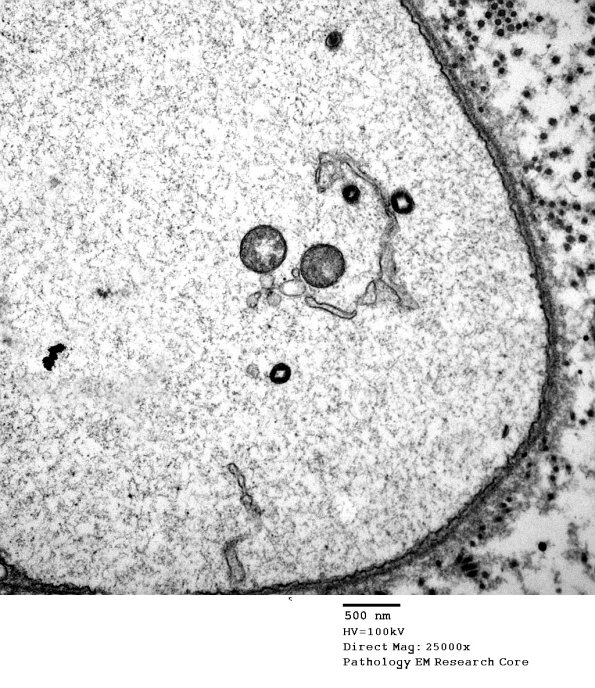

This structure superficially resembles a demyelinated axon although it does not have the expected axonal cytoskeleton and is not accompanied by demyelinated/remyelinated axons. (electron micrographs)